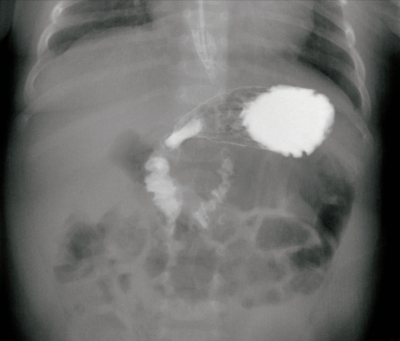

尿所見:蛋白(−)、糖(−)、潜血(−)、尿比重 1.005。血液所見:赤血球 450万、 Hb 13.5 g/dL、Ht 43%、白血球 7,400、血小板 21万。血液生化学所見:AST 38U/L、ALT 28 U/L、尿素窒素 5.4 mg/dL、クレアチニン 0.3 mg/dL、Na 140 mEq/L、K 4.5 mEq/L、Cl 105 mEq/L。CRP 0.1mg/dL。上部消化管造影像を別に示す。

治療として適切なのはどれか。

a. 緊急手術

b. 経管栄養

c. 静脈栄養

d. 制吐薬投与

e. 右側臥位保持